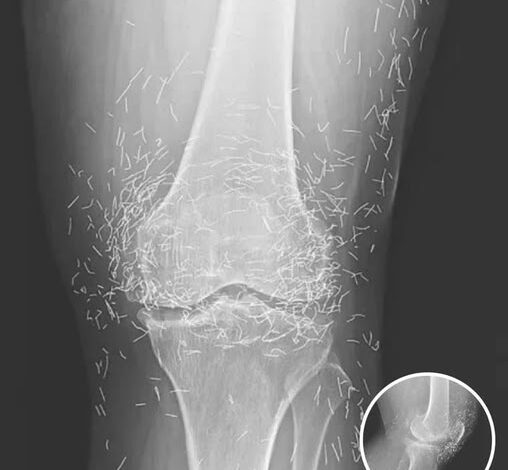

A routine scan in South Korea revealed a 65-year-old woman’s knee was filled with hundreds of tiny gold needles. What she thought was ordinary osteoarthritis pain—stiffness, swelling, and cartilage wear—turned out to be far more unusual.

She had tried standard treatments like painkillers and anti-inflammatories with little relief, so she turned to acupuncture. While generally safe, prolonged or improper techniques can leave retained needles, which may cause inflammation, tissue damage, or infection over time.